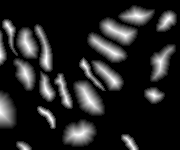

Histopathology image synthesis aims to address the data shortage issue in training deep learning approaches for accurate cancer detection. However, existing methods struggle to produce realistic images that have accurate nuclei boundaries and less artifacts, which limits the application in downstream tasks. To address the challenges, we propose a novel approach that enhances the quality of synthetic images by using nuclei topology and contour regularization. The proposed approach uses the skeleton map of nuclei to integrate nuclei topology and separate touching nuclei. In the loss function, we propose two new contour regularization terms that enhance the contrast between contour and non-contour pixels and increase the similarity between contour pixels. We evaluate the proposed approach on the two datasets using image quality metrics and a downstream task (nuclei segmentation). The proposed approach outperforms Sharp-GAN in all four image quality metrics on two datasets. By integrating 6k synthetic images from the proposed approach into training, a nuclei segmentation model achieves the state-of-the-art segmentation performance on TNBC dataset and its detection quality (DQ), segmentation quality (SQ), panoptic quality (PQ), and aggregated Jaccard index (AJI) is 0.855, 0.863, 0.691, and 0.683, respectively.